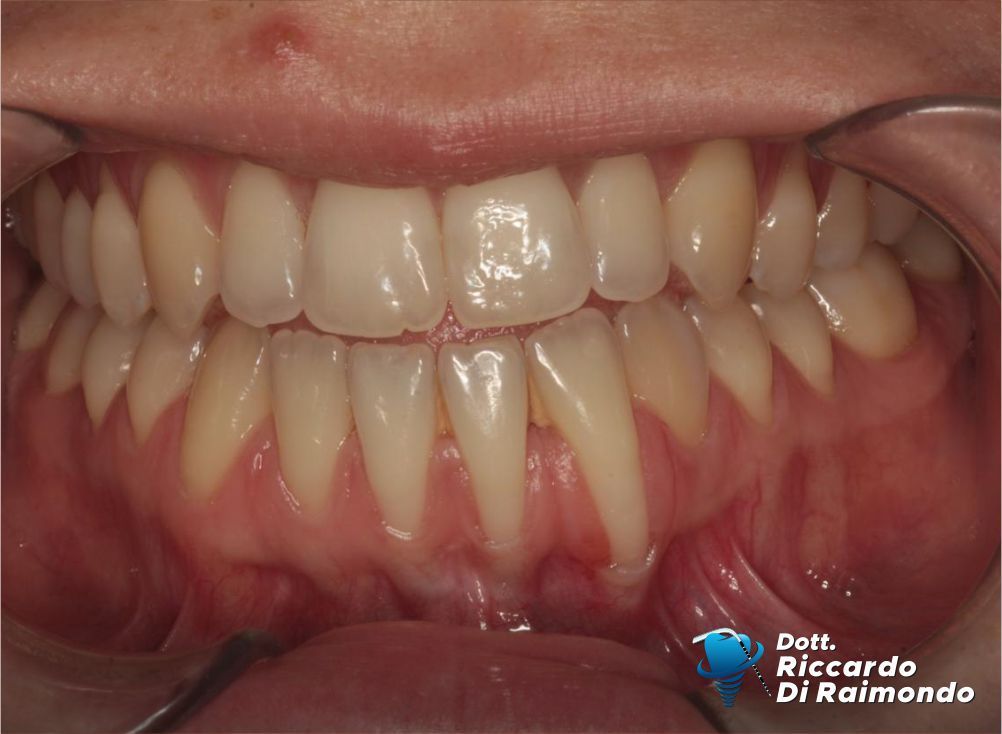

Una paziente di 28 anni si è presentata alla mia osservazione con recessioni gengivali multiple nel settore antero-inferiore. L’esame clinico ha evidenziato la presenza di un fenotipo gengivale sottile, una condizione biologica che rappresenta un importante fattore predisponente allo sviluppo e alla progressione delle recessioni gengivali.

Dall’analisi dell’anamnesi e della storia odontoiatrica è emersa inoltre la possibilità che un precedente trattamento ortodontico, con movimenti dentari eccessivamente vestibolari rispetto ai limiti del processo alveolare, possa aver contribuito alla comparsa delle recessioni.

Prima del Trattamento